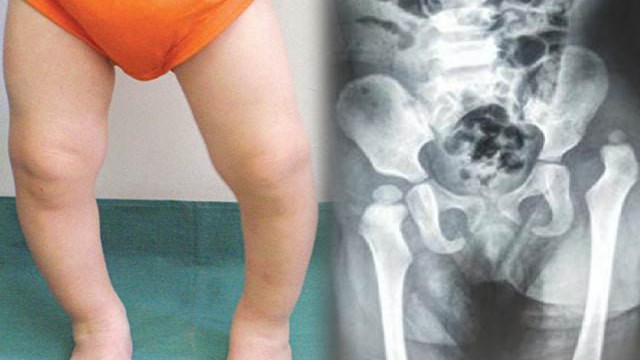

Khớp háng - một phần quan trọng trong hệ thống cơ xương của con người, đóng vai trò quan trọng trong việc hoạt động và di chuyển hàng ngày của mỗi chúng ta. Vậy loạn sản khớp háng tiến triển là gì? Dấu hiệu nhận biết như thế nào? Hãy cùng tìm hiểu qua bài viết dưới đây.